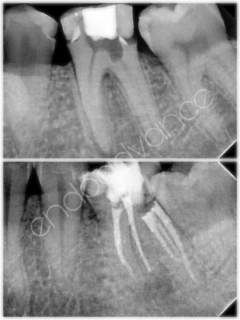

Αρχική ενδοδοντική θεραπεία σε άνω γομφίο με περίπλοκη ανατομία